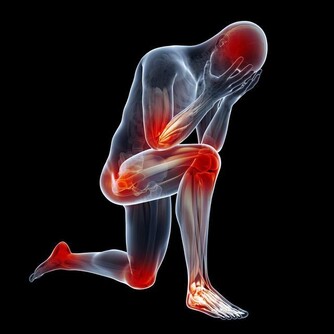

1、許多人到了秋冬季節,因為氣溫開始下降,容易出現手腳冰涼,畏寒怕冷等情況。這些表現是脾虛生寒引起的,如果出現以上病情,需要及時調理好脾臟,才能緩解手腳冰涼症狀。

3、脾虛的人很容易伴隨貧血症狀,常常出現頭暈乏力,精神不振,鬱鬱寡歡,臉色蒼白等症狀。患者可以通過日常飲食攝取足夠的鐵元素,幫助緩解貧血症狀,還可以多進食對脾臟有益的食物,改善脾虛。